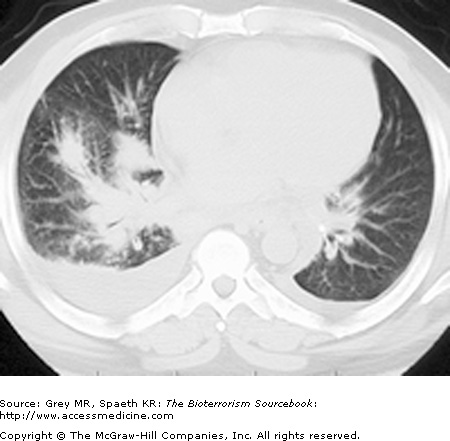

Inhalational anthrax is characterized by a series of radiographic and tomographic changes that can aid greatly in diagnosis. Radiographs provide critical diagnostic information many hours or even days before blood or sputum cultures can turn positive. These changes, when presenting late, indicate a poor prognosis. Computed tomography (CT) taken of the post-September 11 anthrax patients also showed characteristic abnormalities that have substantial diagnostic value. Initial CTs in virtually all of the post-September 11 inhalational anthrax cases were markedly abnormal and had an unusual combination of findings of enlarged hyperattenuating mediastinal and hilar lymph nodes, diffuse mediastinal fat edema, peribronchial thickening, and pleural effusions. Given the rarity of inhalational anthrax in the modern era, this terrorist attack provided valuable information for the presentation of anthrax in the era of CT scans. The findings corroborate the classic chest radiograph findings. CT scans are now considered a standard diagnostic tool for inhalational anthrax. These key radiographic findings are summarized in Table 14–2 (see also Figs. 14–5, 14–6, 14–7, and 14–8).